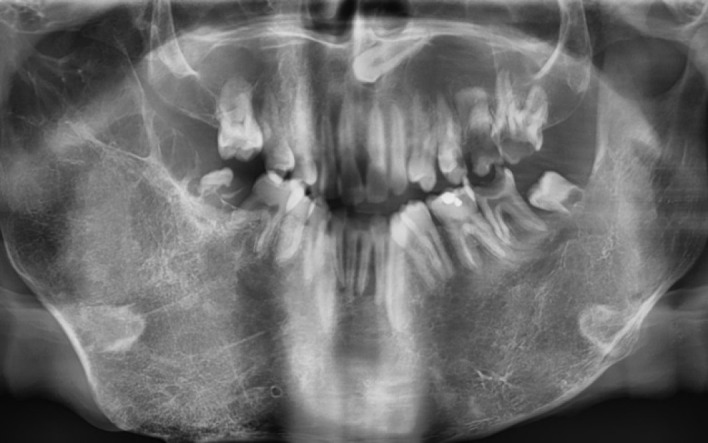

努南综合征是一种以各种系统性问题为特征的遗传病,包括心脏缺陷、身材矮小、出血问题和智力残疾。这种疾病也表现在口腔和颌面区域,突出了牙医在诊断和解决相关并发症中的作用。本报告描述了一名患有努南综合征的15岁男孩的有效牙科治疗,该男孩患有几种口腔和牙齿问题,在9个月的随访期间临床和放射学无症状。了解努南综合征患者的医疗状况和口腔面部表现可以有效地确定更好的治疗计划,提供更有效和更安全的治疗,并随后改善长期预后。

Noonan syndrome is a genetic condition characterized by various systemic issues, including cardiac defects, short stature, bleeding problems, and intellectual disabilities. This disorder also shows several manifestations in the oral and maxillofacial region, highlighting the dentist's role in diagnosing and addressing related complications. This report represents the effective dental management of a 15-year-old boy with Noonan syndrome who suffered from several oral and dental problems and was clinically and radiographically asymptomatic in a nine-month follow-up session. Awareness of the medical conditions and orofacial manifestations of patients with Noonan syndrome can be effective in determining a better treatment plan, providing more effective and safer treatment, and subsequently enhancing the long-term prognosis.